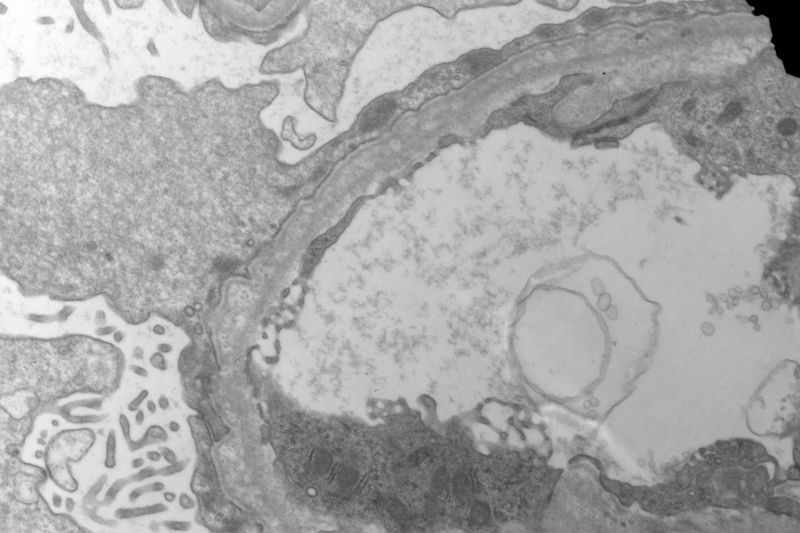

Sixty old man with proteinuria and hematuria

• Sixty old man with proteinuria and hematuria图1

图1

Picture 2 you fisrt posting showed a lot of foamy cells and some things like HP  in a tubular cavity in the centre of picture. About picture 7, i can see one capillary loop and its endothelial cell, i'm doute of  like a tadpole someting different in the capillary cavity , can you tell me, thank you very much.

Yes, I agree with your observation that there are a lot of foamy cells. The most impressive change is the lamination or splitting of the glomerular basement membrane.

Thank you,to combine the splitting of the glomerular basement membrane with a lot of foamy cells infiltration, I first take into account Alport Syndrome, but the age of the patient is too old, so Alport Syndrome seems unlikely. Under LM, the glomerulosclerosis and tubular atrophy/interstitial fibrosis. Please comment, thank you

The patient has a long history of "chronic kidney disease". Initially, he did not tell the nephrologist that he started to have kidney disease decades ago. Given the characteristic ultrastructural changes, Alport's syndrome is suggested.